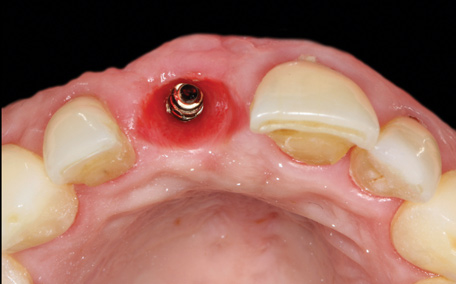

4. Facial and occlusal views of initial clinical presentation of tooth No. 8.

Figure 4

5. Facial and occlusal views of initial clinical presentation of tooth No. 8.

Figure 5